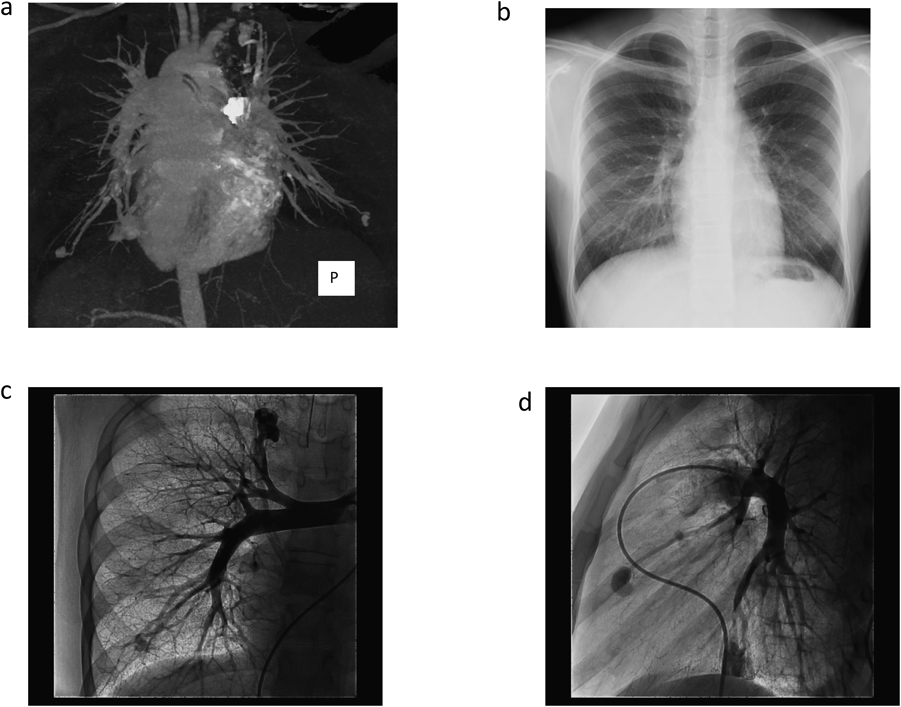

Fig. 2 Contrast-enhanced computed tomography (CT)

(a) and Chest X-ray (b) which were performed as an initial PAVMs screening examination, Pulmonary angiography (PA) which was performed at the time of coil embolization. A frontal view of the right selective pulmonary artery angiogram (c), A lateral view of the left selective pulmonary artery angiogram (d).

血液検査(Table 1)では異常所見なし.胸部レントゲン(Fig. 2b)では心胸郭比43%,両肺野に淡い腫瘤影を認めた.

肺動脈圧17/7(10)mmHgと肺高血圧は認めなかった.

左右肺動脈造影(Fig. 2c, d)にてCTと同様のPAVMを確認した.左S8病変は2本以上の肺動脈が2本以上の肺静脈に流入する複雑型であった.大きな病変より順にCEを施行した.CEは基本的に瘻内より流入血管まで留置することとし,着脱式マイクロコイル:Micrus™microcoils(J&J, Codman)のPRESIDIOにてframing,DELTAMAXXにてfillingを行う方法で塞栓した(Fig. 3).カテーテルは複雑型で血流の多い左S8病変のみオクリュージョンカテーテル:OPTIMO 6F(Tokai Medical)を使用,その他病変に対してはコブラ4F(Terumo)とPROWLER SELECT PLUS45°(J&J, Codman)にて安定した留置が可能であった.